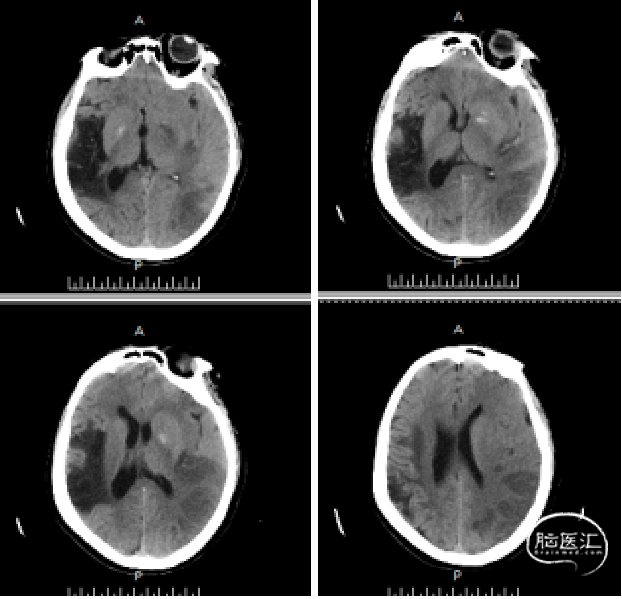

患者发病6小时,头颅CT排除颅内出血,急性起病、意识不清、失语、双眼向左侧凝视、右侧肢体瘫痪。患者急性脑梗死诊断明确,超出静脉溶栓时间窗,有动脉机械取栓治疗指征。经过与家属的充分沟通,家属理解手术风险,同意手术治疗。选择右侧股动脉穿刺置管,给予脑血管造影术+动脉取栓术。

术后24小时复查头颅CT未见颅内出血。

患者术后24小时拔除气管插管,神志清楚,精神可,言语欠清,双侧瞳孔等大等圆,直径3mm,对光反射灵敏,颈软,心律齐,未闻及杂音,双肺呼吸音稍粗,未闻及干湿性啰音,右侧上下肢体肌力4级,左侧肌力5级、肌张力正常,双侧巴氏征阴性。术后24小时 GCS:15分,NIHSS:2分,mRS:1分。

术后15随访情况:7天后患者NIHSS改善。2周后随访,患者无明显肢体功能障碍,mRS评分为0分。